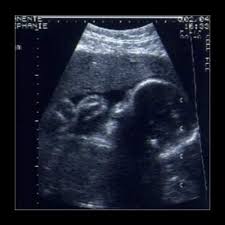

Baby gewicht 30 ssw. Das Gewicht klettert auf etwa 1400 Gramm. Da es im Bauch für das Baby immer enger wird nimmt es allmählich die Fötusstellung ein. Soziale Netzwerke Snapchat.

So entwickelt sich Dein Baby. Es lutscht jetzt oft am Daumen und reagiert auf Reize von außen. Dein Baby ist jetzt 40 cm lang - mit dem Ausstrecken im Bauch ist endgültig Schluss.

Auf 38 Zentimeter Körperlänge bringt es nun Ihr Baby in der 30. Wegen des Platzmangels verschränkt es die Arme zieht die Beinchen an und neigt das Kinn zur Brust. SSW misst der Oberschenkelknochen ungefähr 58 cm.

Mithilfe dieses Wertes lässt sich das derzeitige Gewicht Deines Babys schätzen.

In der 30. Ihr Baby in SSW 28. Glicemia e pressão tudo Ok. Größe Scheitel-Fersen-Länge SFL Größe Scheitel-Steiß-Länge SSL Gewicht. Da es im Bauch für das Baby immer enger wird nimmt es allmählich die Fötusstellung ein. Ihr Baby in SSW 21. Wegen des Platzmangels verschränkt es die Arme zieht die Beinchen an und neigt das Kinn zur Brust. Ein Baby der 30. Es zieht Ärmchen und Knie an und legt das Kinn auf die Brust.

Das Baby hat in der 30. Bei einer Frühgeburt in der 30. Es lutscht jetzt oft am Daumen und reagiert auf Reize von außen. Die Reifung der Lungen und des Verdauungstraktes sind bald abgeschlossen und die Organe sind fast vollständig ausgebildet. Fiz a ultra com 31 semanas e neném ja esta com 2200kg e 45cm. Woche nach der Befruchtung. Ihr Baby in SSW 27.